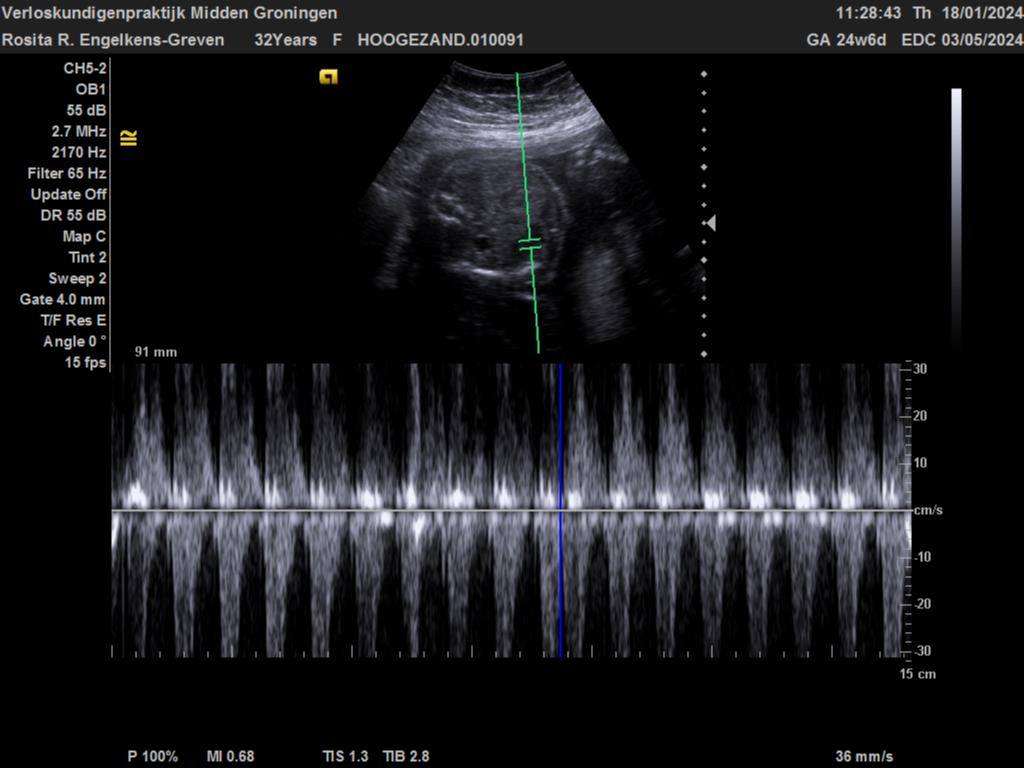

Echo 24 week en 6 dagen zwangerschap

Hierboven zie je een mooie echo van haar gezichtje en een beentje in beeld. Ze is al een echt eigenwijs meisje aan het worden want zodra wij willen gaan kijken met de echo ja dan werkt zij echt heel erg tegen. Maar dat niet alleen hoor, Omdat ze zo laag ligt is het ook echt wel heel erg moeilijk om een goede echo te gaan krijgen. Maar alle mooie beeldjes die wij kunnen krijgen daar zijn wij heel erg blij mee.